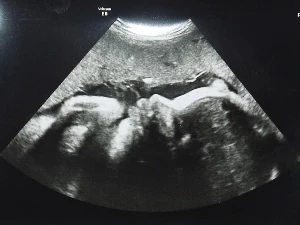

Voltam szülésznőnél, de a szokásos vizsgálatokon kívül (vérnyomás mérés, vizeletvizsgálat, pocakmérés, fogdosás, szívhanghallgatás) nem volt semmi. Nem tudom, mennyire egyértelmű, de itt az egész terhesség alatt - ha egyébként nem indokolt - egyáltalán nincs hüvelyi vizsgálat. Azt hiszem, ezt a részét szeretem legjobban az itteni rendszernek! Persze, nem tudom, milyen épp a méhszájam állapota, de egyébként nem mindegy? Van, aki nyitott méhszájjal is heteket van talpon, és van, aki pár óra alatt kinyílik, és már szül is. Inkább az számít, hogy mit érzek, hol érzem, fáj-e valahol, kellemetlen-e. És ezt szépen meg is kérdezik, részletesen meghallgatnak mindent, amit el akar mondani a kismama. Én mondtam, hogy szurkál a méhszájam, sokat keményedik a pocakom, és talán többet kellene feküdnöm. A szülésznő szeme azonban felcsillant, és mosolyogva mondta, hogy akkor ebből nem valószínű, hogy túlhordás lesz, időszerű a méhszáj kivékonyodása. A keményedésre fel sem merült az otthon megszokott magnézium ipari mennyiségben való fogyasztása! Örült, hogy Braxton-Hicks összehúzódásaim vannak. Mondtam, hogy én azt hittem, azok fájdalommal is járó kontrakciók (magyarul Braxton-Hicks fájásoknak vagy jósló fájásoknak nevezzük, ugye, őket), de azt mondta, hogy egyáltalán nem kell, hogy valós fájdalom is társuljon hozzájuk.

Szóval mosolyogva jöttem el, abban a reményben, hogy a 40. heti időpontra már nem is kell mennem, mert addigra megszületik ez a kicsi lány!